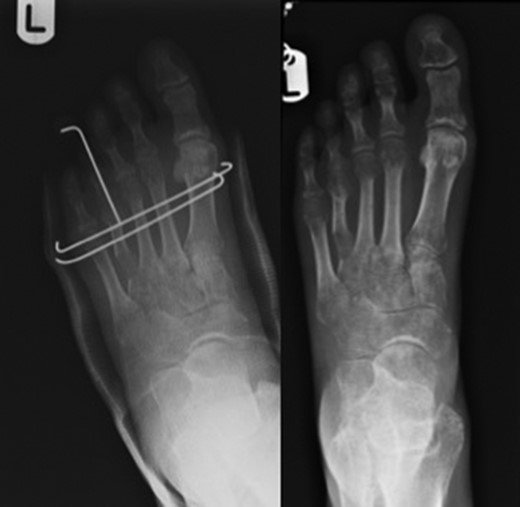

The aim of this prospective case series is to assess outcomes and complications of a novel technique for gradual metatarsal lengthening using a circular fixator followed by trans-metatarsal k-wire fixation. The circular external fixator applies Ilizarov principles which describes the importance of increased frame stability and thus better control of alignment and reduced subluxation [5]. The trans-metatarsal k-wires (Fig. 3), placed after removal of the external fixator, prevents further subluxation. We theorise that using a circular external fixator followed by trans-fixation metatarsal k-wires could reduce complication rates associated with distraction osteogenesis using external fixators and potentially improve the healing time along with restoration of metatarsal parabola and subsequently improving the biomechanics of the forefoot (Fig. 4).

Pre-operative image on the left with image on the right showing successful lengthening.